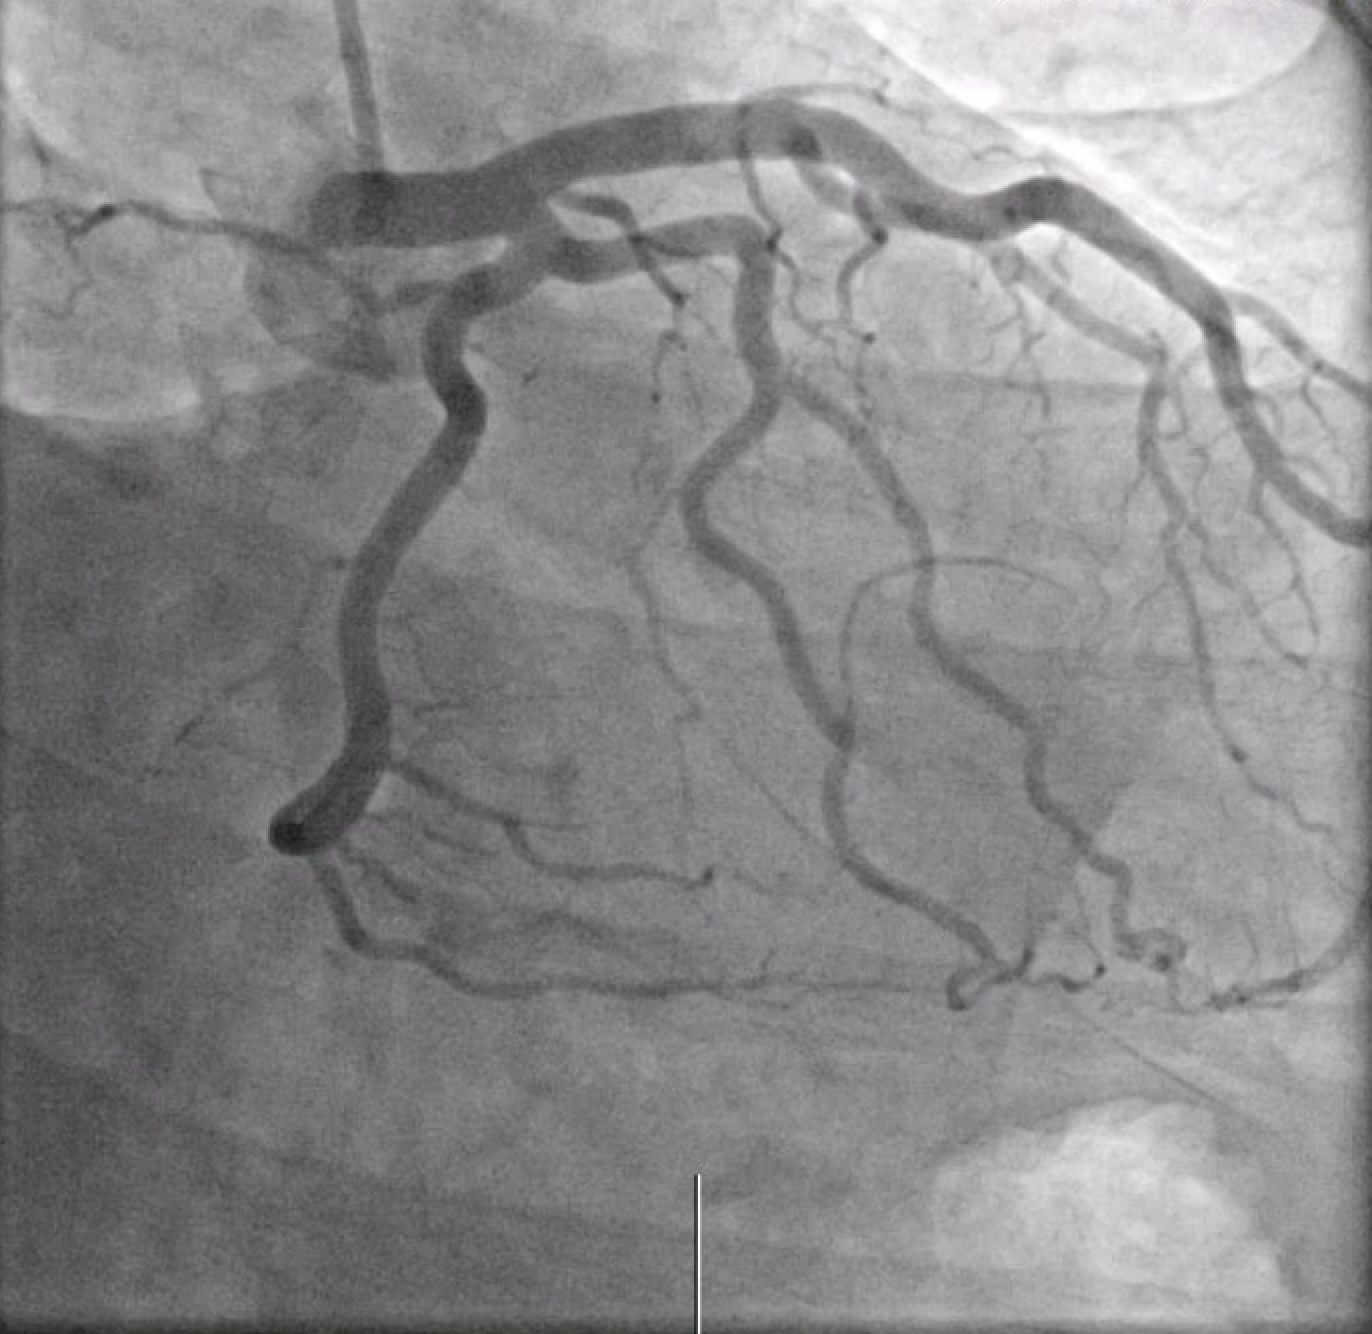

A 36-year-old male with a history of well-controlled HIV on ART, presented with fever, hypotension, and a morbilliform rash shortly after initiation of trimethoprim-sulfamethoxazole for a skin and soft tissue infection. He was found to have elevated troponins (peak 661 ng/L) and diffuse ST elevations on EKG, consistent with myopericarditis. He was vitally stable and did not complain of chest pain or shortness of breath throughout his hospital course. Initial investigation with coronary CTA revealed a possible LM thrombus, which was confirmed on left heart catheterization (LHC) as a non-obstructive thrombus (30% stenosis) in the mid-LM. The patient was managed with a tirofiban bolus and infusion, a heparin drip, and dual antiplatelet therapy with aspirin and clopidogrel. Repeat LHC five days later demonstrated complete resolution of the thrombus. TEE was performed to exclude possible sources of embolization including valvular vegetation or left ventricular thrombus. This was notable for a small mobile echodensity on the tricuspid valve which appeared to be consistent with redundant tissue, but no left-sided source of embolism, and he did not have evidence of a patent foramen ovale. The patient was discharged on apixaban and clopidogrel for 6 and 12 months respectively, with plans for outpatient cardiology follow-up and cardiac MRI.